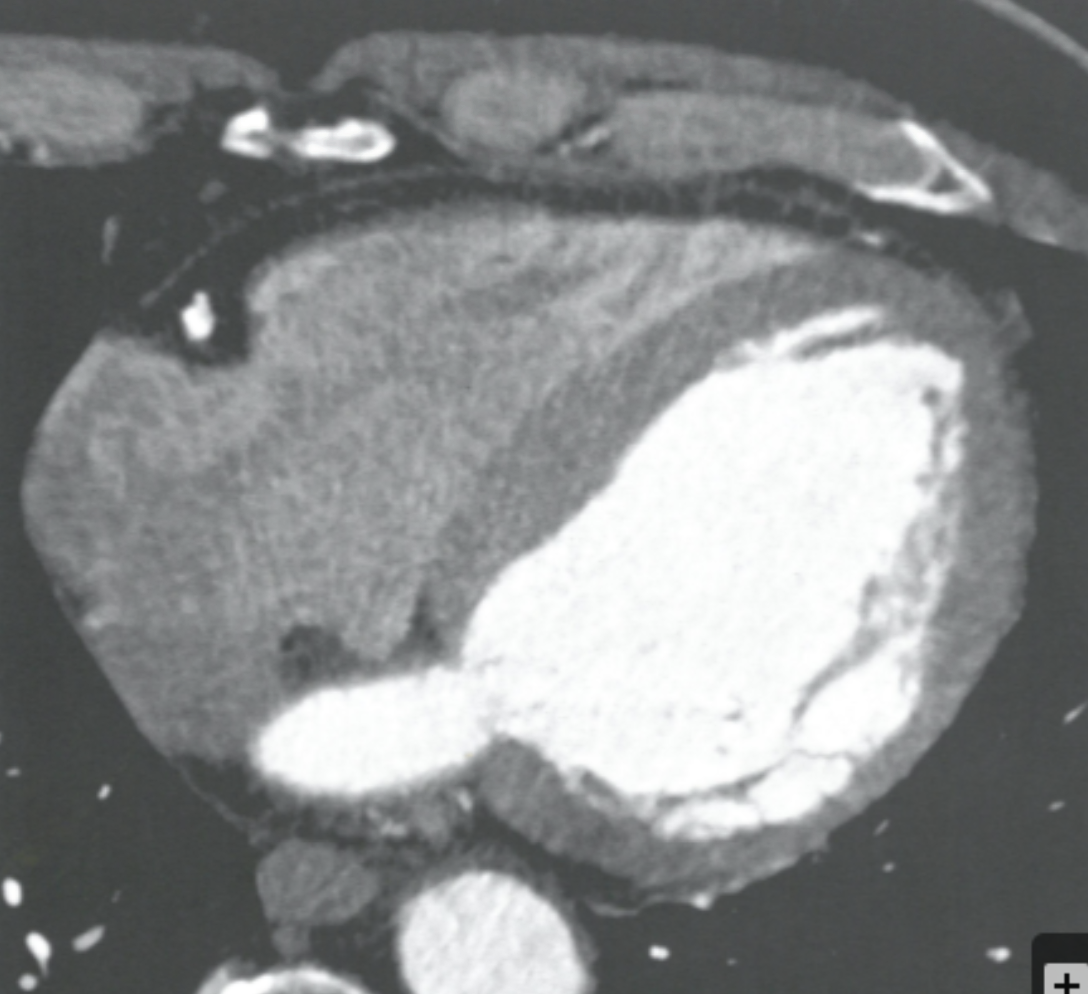

What is the role of CCTA as it pertains to evaluating for ischemic heart disease in the setting of heart failure?

May offer a valid alternative to invasive angiography in diagnosing ischemic heart failure in patients with reduced EF